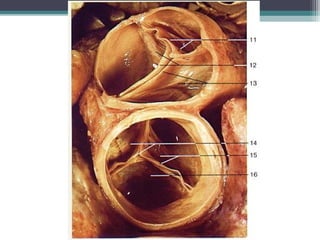

Ventrículo esquerdo

Objetivos:

Valva atrioventiucular

tricúspide;

Valva aórtica

Músc. Papilar anterior,

M~usc. Papilar posterior

Ventrículo esquerdo Objetivos: Valva atrioventiucular tricúspide; Valvaaórtica Músc. Papilar anterior, M~usc. Papilar posterior